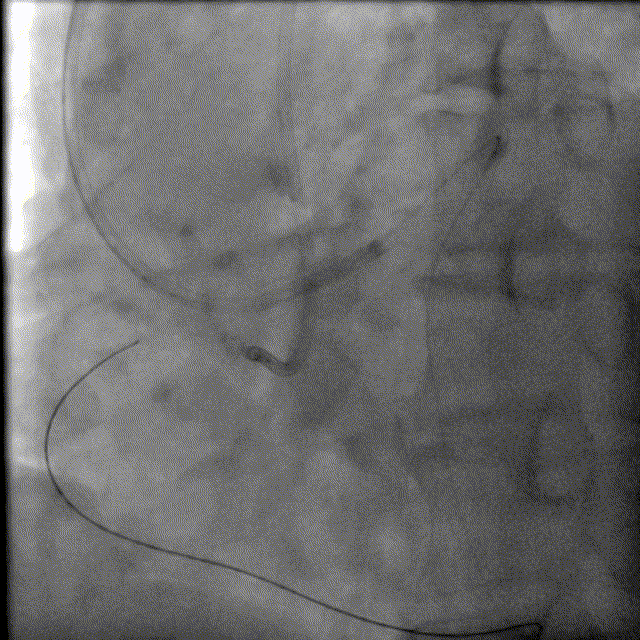

130cm Finecross微导管穿Runthrough 指引导丝到达RCA近端病变处,Fielder XTA、Pilot200指引导丝反复尝试无法通过RCA闭塞病变,随后尝试逆向侧枝开通RCA病变。

150cm Finecross微导管,Sion、Sion black指引导丝反复尝试无法通过LAD-RCA间隔支侧枝及心外膜侧枝血管有困难。

重复造影无造影剂渗漏。

换用较为粗大的心外膜侧。

换用Instantpass微导管(170cm)支撑下送Fielder XT-R导丝通过LAD-RCA心外膜侧枝逆向通过RCA闭塞病变,推送微导管后交换Gaia Third导丝,RCA正向送Telescope™导引延长导管进行主动迎接Gaia Third导丝。